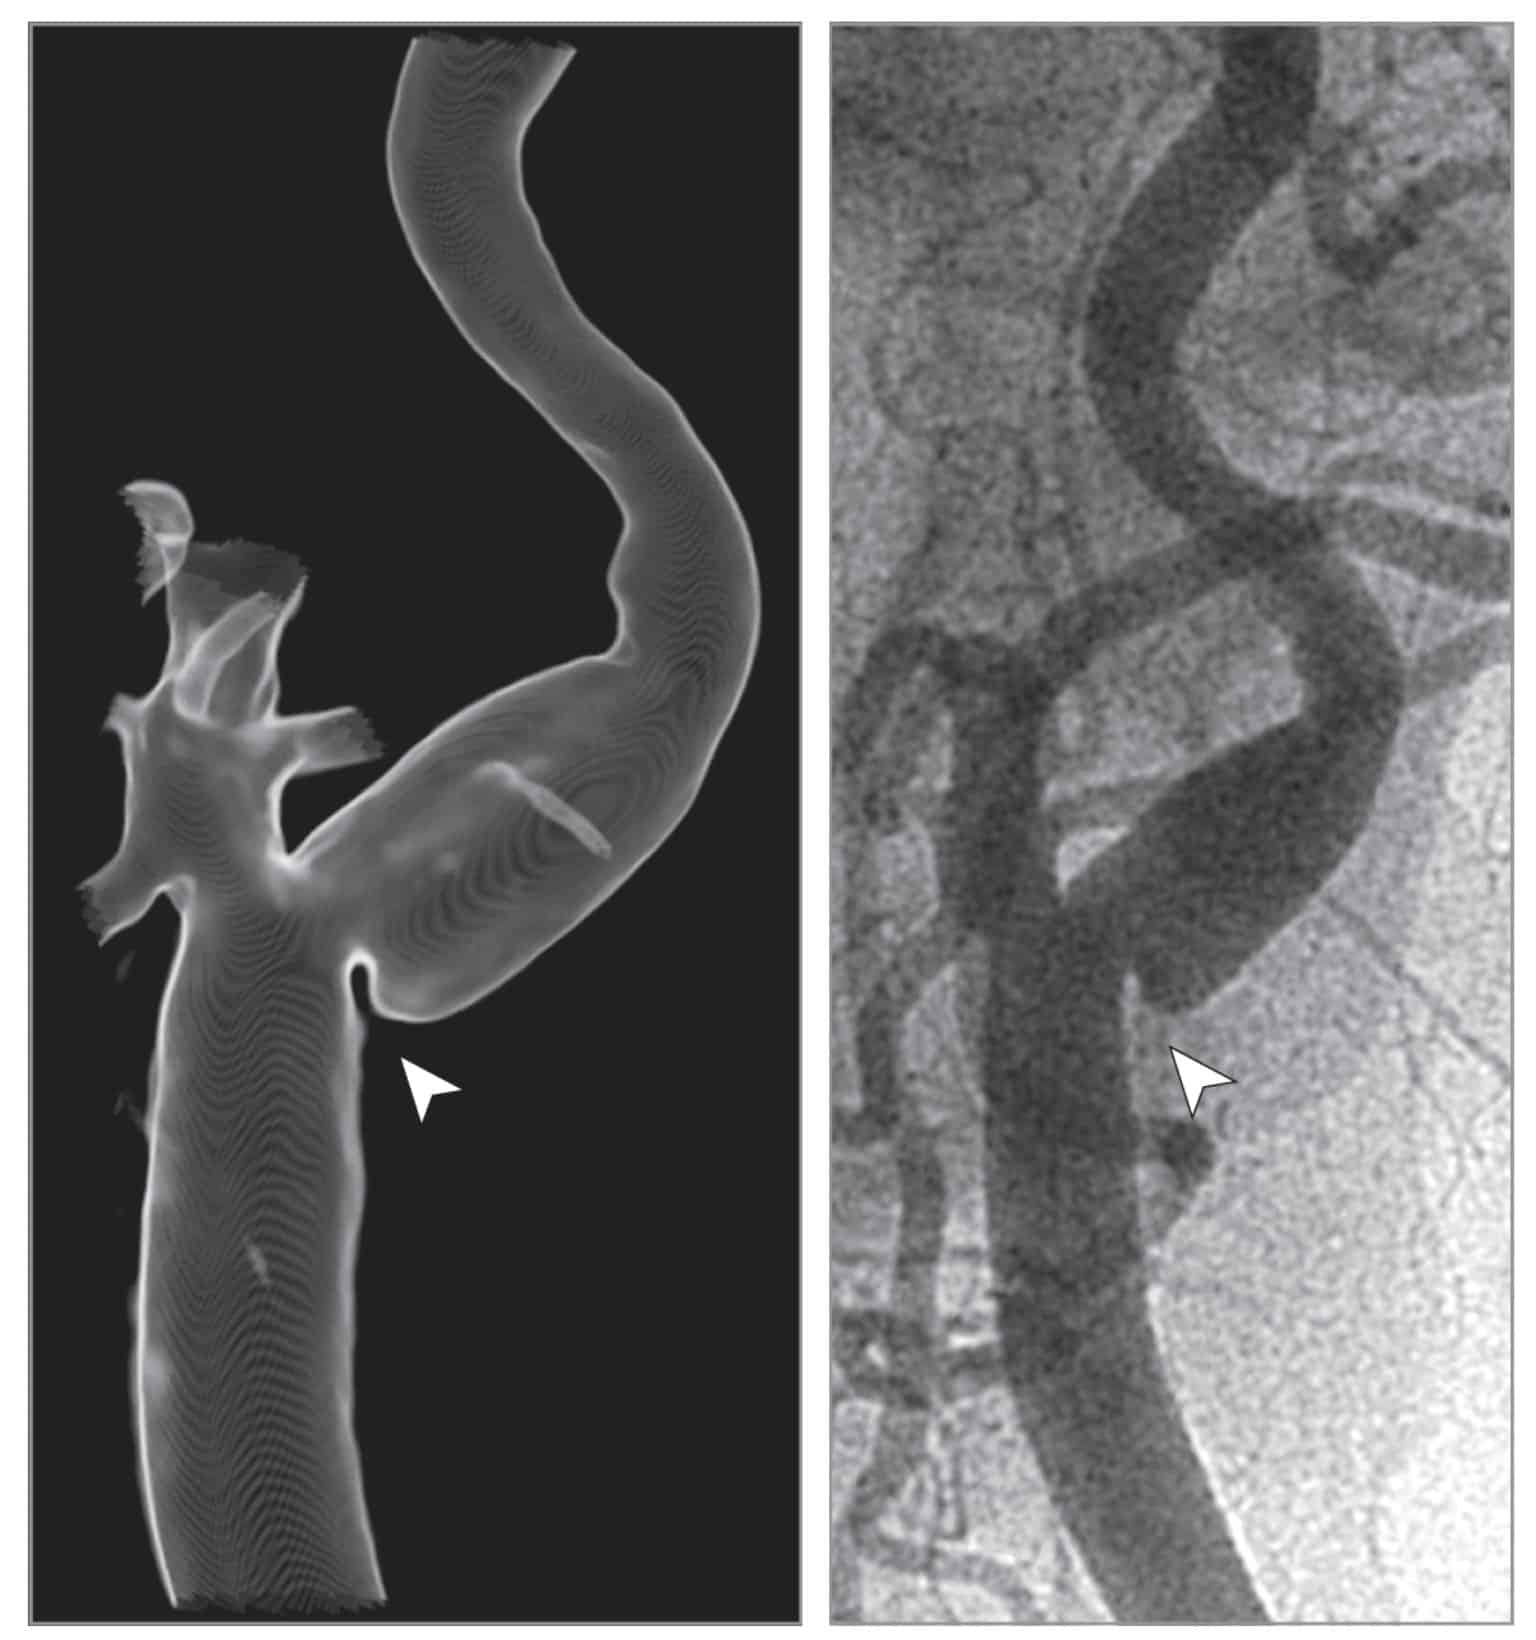

O diagnóstico da web de carótid é feito por meio de exames de imagem que avaliam os vasos do pescoço, como o ultrassom com doppler, a angiotomografia computadorizada ou a angioressonância magnética.

Esses exames permitem visualizar a anatomia das artérias cervicais e identificar a presença da membrana anormal na carótida interna. Em geral, a tomografia e a ressonância são melhores que o ultrassom para identificar os web carotídeos.

Nos casos duvidosos ou quando o tratamento é proposto, a angiografia cerebral pode ser indicada e é o melhor exame para o diagnóstico dos carotid webs.